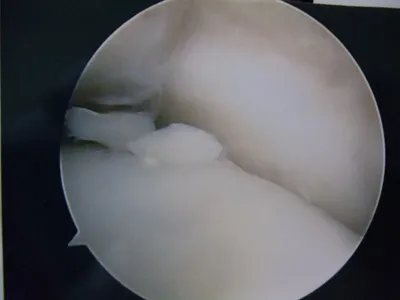

Pic during microfracture of tibial OCD.